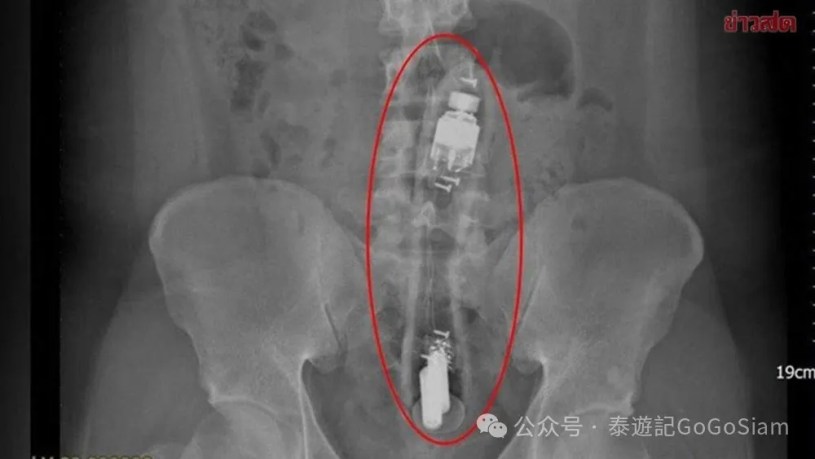

颐达医院结直肠外科医生给这位24岁的男性患者拍摄X光后,发现的确有一长约15至20厘米的物体卡在乙状结肠处。

当值医生解释说,一般性娱乐表面光滑的异物很难简单拔出,因此医生需要进行手术麻醉安全处理。但患者却接受了更为激进的治疗方案,医疗队在急诊手术室最终用类似妇科的产钳的工具深入患者体内取出异物。患者甚至在没有注射麻药的情况下,很好地忍受了疼痛,将这个长物体慢慢取出。